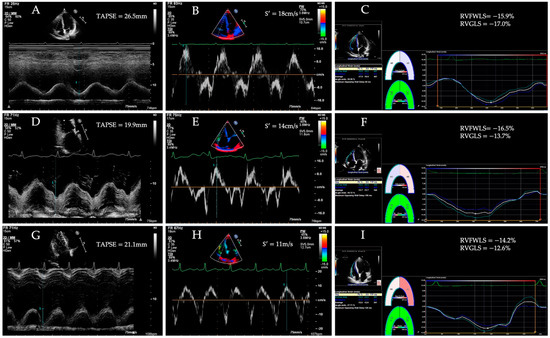

In recent years, two-dimensional speckle tracking echocardiography (2D-STE) has been developed as a new imaging tool of evaluating cardiac function. 2D-STE is the two-dimensional tracking of unique speckle patterns created by the constructive and destructive interference of ultrasound beams within myocardial tissue [46]. 2D-STE allows a precise quantification of RV strain and an early detection of the subclinical RV dysfunction, providing comprehensive diagnostic and prognostic information in patients with a variety of cardiovascular diseases [16,47,48,49,50,51,52,53,54]. RVLS is measured in the RV-focused apical four-chamber view, which provides better visualization of the whole right ventricle, and avoids foreshortening of the RV apex [22]. The frame rate is between 60 and 80 frames per second. The high-quality images are essential for RV strain analysis [55]. After endocardial border delineation, the software automatically segments the right ventricle into six segments (basal, middle, and apical segments of both the RV free wall and the interventricular septum), and tracks the movement of speckles in the myocardium throughout the cardiac cycle on two-dimensional echocardiographic images [56]. Finally, RV longitudinal strain curves of free wall and septum are automatically generated by the software (Figure 1). The average value of longitudinal strain of the basal, middle, and apical segments of the RV free wall is longitudinal strain of the RV free wall (RVFWLS), whereas RV global longitudinal strain (RVGLS) represents the average value of RV six segments [57,58,59]. RVGLS may be affected by LV systolic function owing to the fact that the interventricular septum is conventionally regarded as one part of the left ventricle. Therefore, the published guideline of the ASE and the European Association of Cardiovascular Imaging (EACVI) recommend a normal value only for RVFWLS [60].

Figure 1. Longitudinal strain of the RV free wall and septum using two-dimensional speckle tracking echocardiography.

7. RV Longitudinal Strain in HF Patients with Preserved Traditional RV Function Parameters

Several studies have reported the predictive value of RV longitudinal strain in HF patients with preserved conventional RV systolic function parameters, such as TAPSE and S′. However, these traditional RV function indicators could not accurately assess and represent global RV systolic performance because they only reflected segmental function of the right ventricle [35,88]. RVLS, as a new echocardiographic parameter, overcomes the limitation of angle dependency of TAPSE and S′, and it has incremental clinical value in detecting subclinical RV dysfunction. The current findings regarding RV longitudinal strain in patients with preserved traditional RV function parameters are depicted in Table 3. Morris et al. [89] compared 218 patients with HFpEF and 208 patients with HFrEF with controls and measured RVGLS and RVFWLS by 2D-STE. They found that the normal range of RV systolic strain in the normal population was as follows: 2D-RVGLS −24.5 ± 3.8% and 2D-RVFWLS −28.5 ± 4.8%. They demonstrated that the conventional echocardiographic parameters such as TAPSE, S’, RVFAC in patients with HFpEF or HFrEF were within the normal range, but both 2D-RVGLS and 2D-RVFWLS decreased. Their findings indicated that 2D-RVGLS and 2D-RVFWLS were related to the clinical status of patients with HF. More importantly, subtle RV longitudinal systolic dysfunction can be detected by both 2D-RVGLS and 2D-RVFWLS in a considerable proportion of patients with HFrEF and a smaller group of patients with HFpEF despite preserved TAPSE, RVFAC and S’. Carluccio et al. [24] demonstrated that 2D-RVFWLS is impaired in patients with HFrEF with preserved TAPSE. According to the lasso-penalized Cox-hazard model, impaired 2D-RVFWLS was an independent predictor of death and HF rehospitalization, providing incremental prognostic value over TAPSE and other recognized clinical and echocardiographic predictors of end points and improving risk stratification. The best cutoff value of 2D-RVFWS for prediction of outcome was −15.3%. The results of this study also demonstrated the potential of RVLS in detecting subtle RV systolic dysfunction. Three case examples of altered RV strain despite preserved TAPSE and S-TDI in patients with HFpEF, HFmrEF and HFrEF are shown in Figure 3.

Figure 3. Tricuspid annular plane systolic excursion (TAPSE), systolic velocity of the tricuspid annulus (S’), longitudinal strain of the RV free wall and RV global longitudinal strain in patients with HFpEF (AC), HFmrEF (DF) and HFrEF (GI).